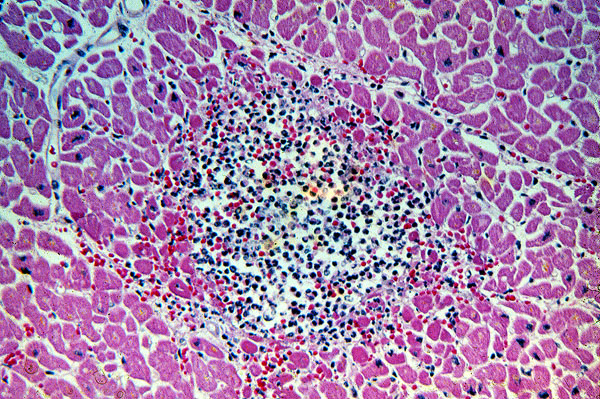

Septic embolus, heart, microabscess, Candida albicans

This patient had a prosthetic aortic valve that was infected with the common yeast, Candida albicans. A portion of the vegetation embolized from the valve into the coronary artery, and a microabscess within the myocardium was the result.